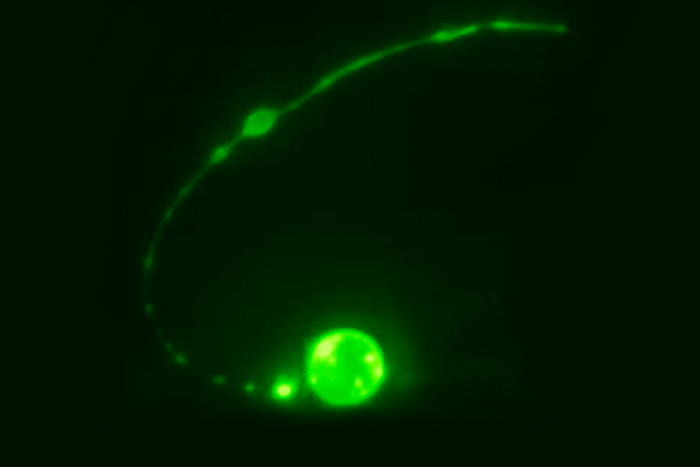

Studying microscopic worms, Rockefeller scientists have identified a brain circuit that drives repetitive behavior—providing potential clues for understanding some human psychiatric conditions.